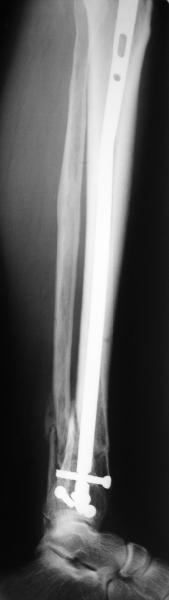

A typical case is attached, also an image with intra-op reduction obtained by a small wire distractor, in the moment of insertion a Poller wire in AP direction. Fixation by a SIGN nail. Despite the fibula was not fixed healing was obtained with the unchanged alignment.

Very interesting application, but is the final position in a little distal varus with some fibula

distraction? Would that have been eliminated by fibula plating?

At least both the ankle mortise and tibial alignment look acceptable, don't they?

I am just trying to illustrate that prevention of 1)tibial valgus and 2)loss of reduction can be provided without fibular plating. Small changes of conventional nailing techniques allow to maintain reduction of the tibia reliably without adjunctive fibular stabilization.

In delayed cases acute length restoration performed only in the tibia may leave the fibula shortened thus change the mortise. So it is reasonable to restore length of both bones simultaneously by distractor and fix the fibula not with open reduction and plating but just by a single perQ screw. Example attached.